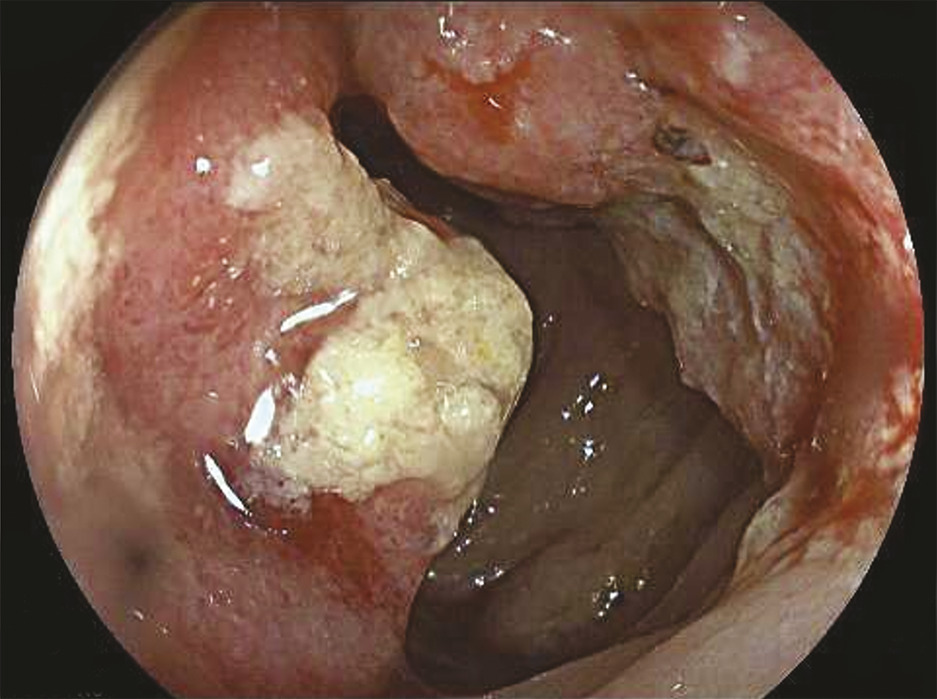

La coloscopie, sous anesthésie générale, est l’examen de première intention dans la plupart des cas de rectorragies. Si elle met en évidence une tumeur rectale, elle peut être complétée immédiatement ou dans un second temps par une rectoscopie rigide, permettant d’évaluer plus précisément la distance entre le pôle inférieur de la tumeur et la marge anale (mesure la plus reproductible) et/ou le pôle supérieur du sphincter. L’examen endoscopique permet également de décrire la lésion rectale (taille, aspect macroscopique, circonférence d’implantation) et de recueillir de multiples biopsies, indispensables au diagnostic (fig. 1 et 2 ).